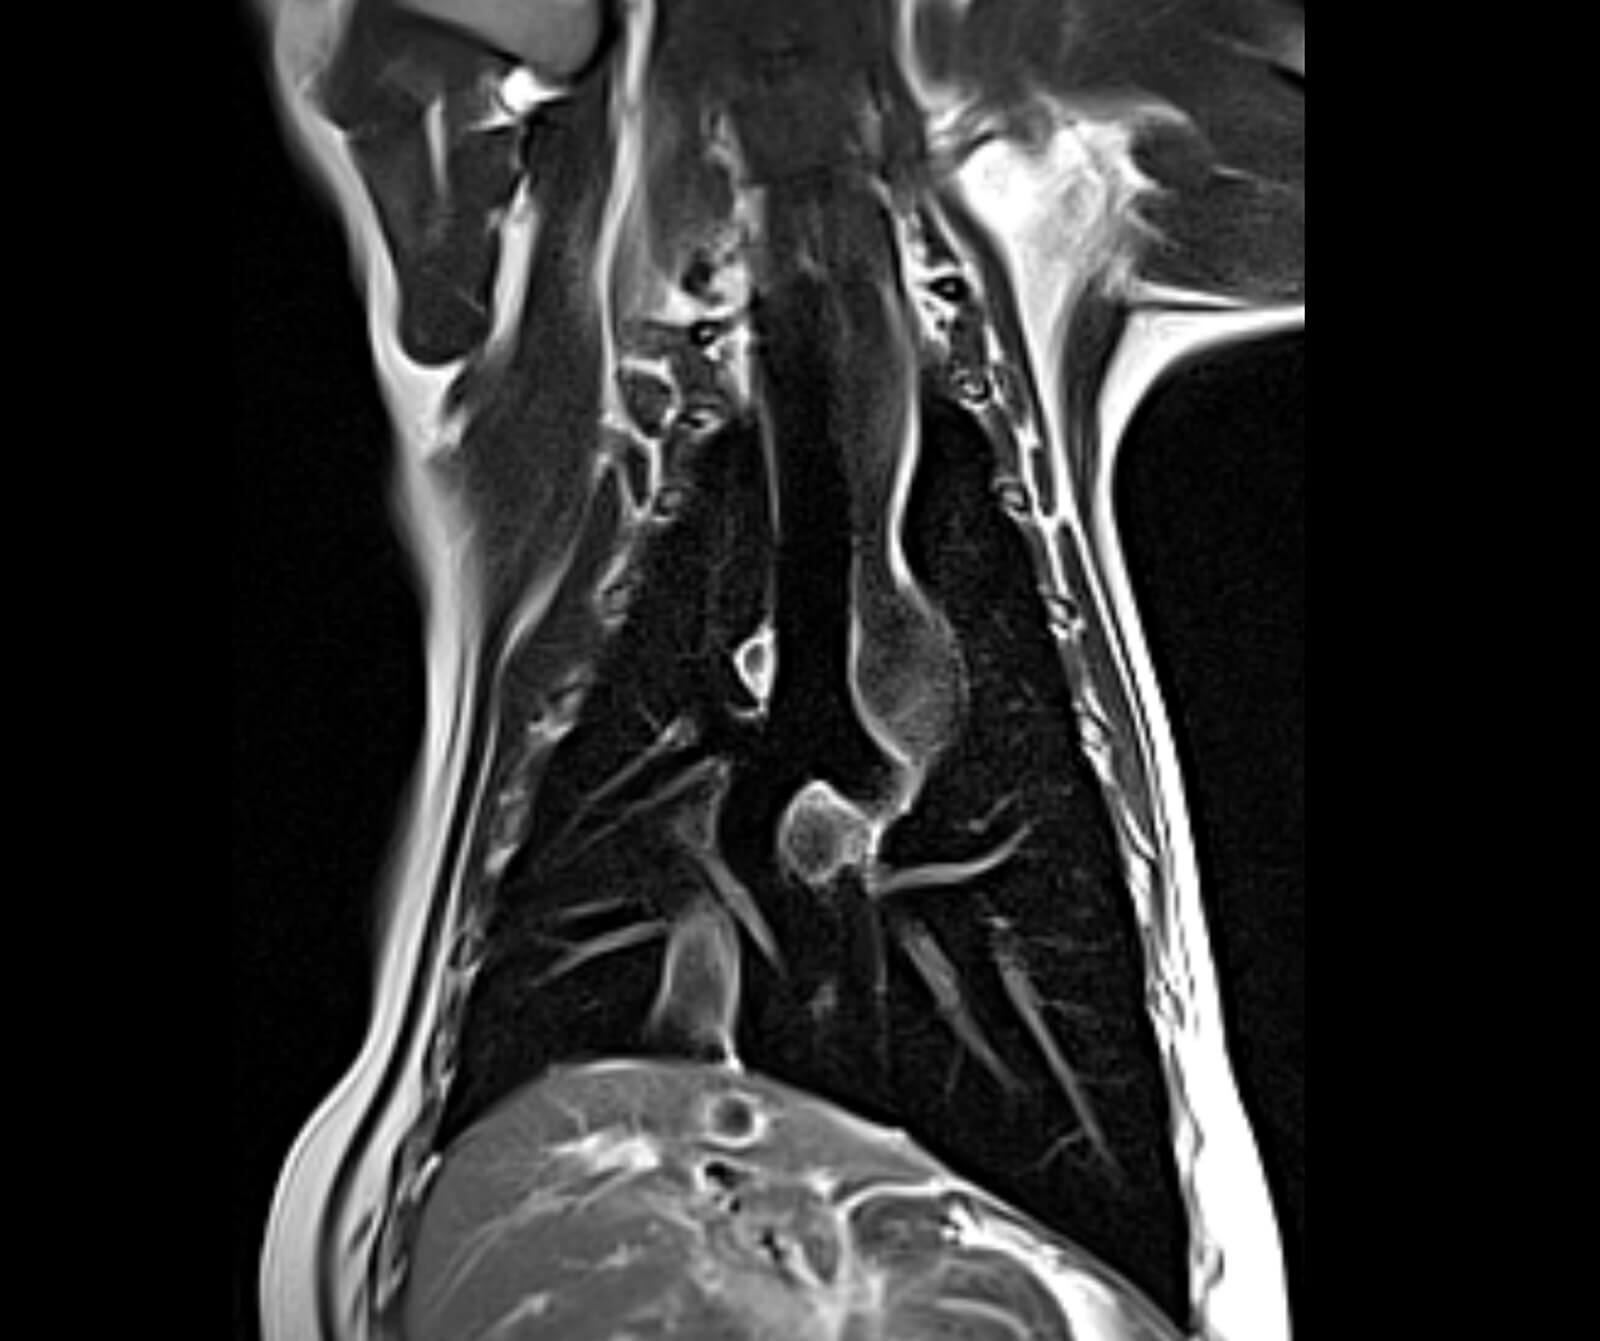

Veteriner hekimliğinde MR; beyin, omurilik, sinir sistemi, kas-iskelet sistemi ve iç organ hastalıklarının değerlendirilmesinde kritik rol oynar. Kemik yapılar dâhil olmak üzere vücudun tüm bölgeleri MR ile ayrıntılı şekilde incelenebilir.

• Beyin ve nörolojik hastalıkların değerlendirilmesi

• Spinal kord incelemeleri

• Tümörler, felç, beyin kanamaları ve damar tıkanıklıkları